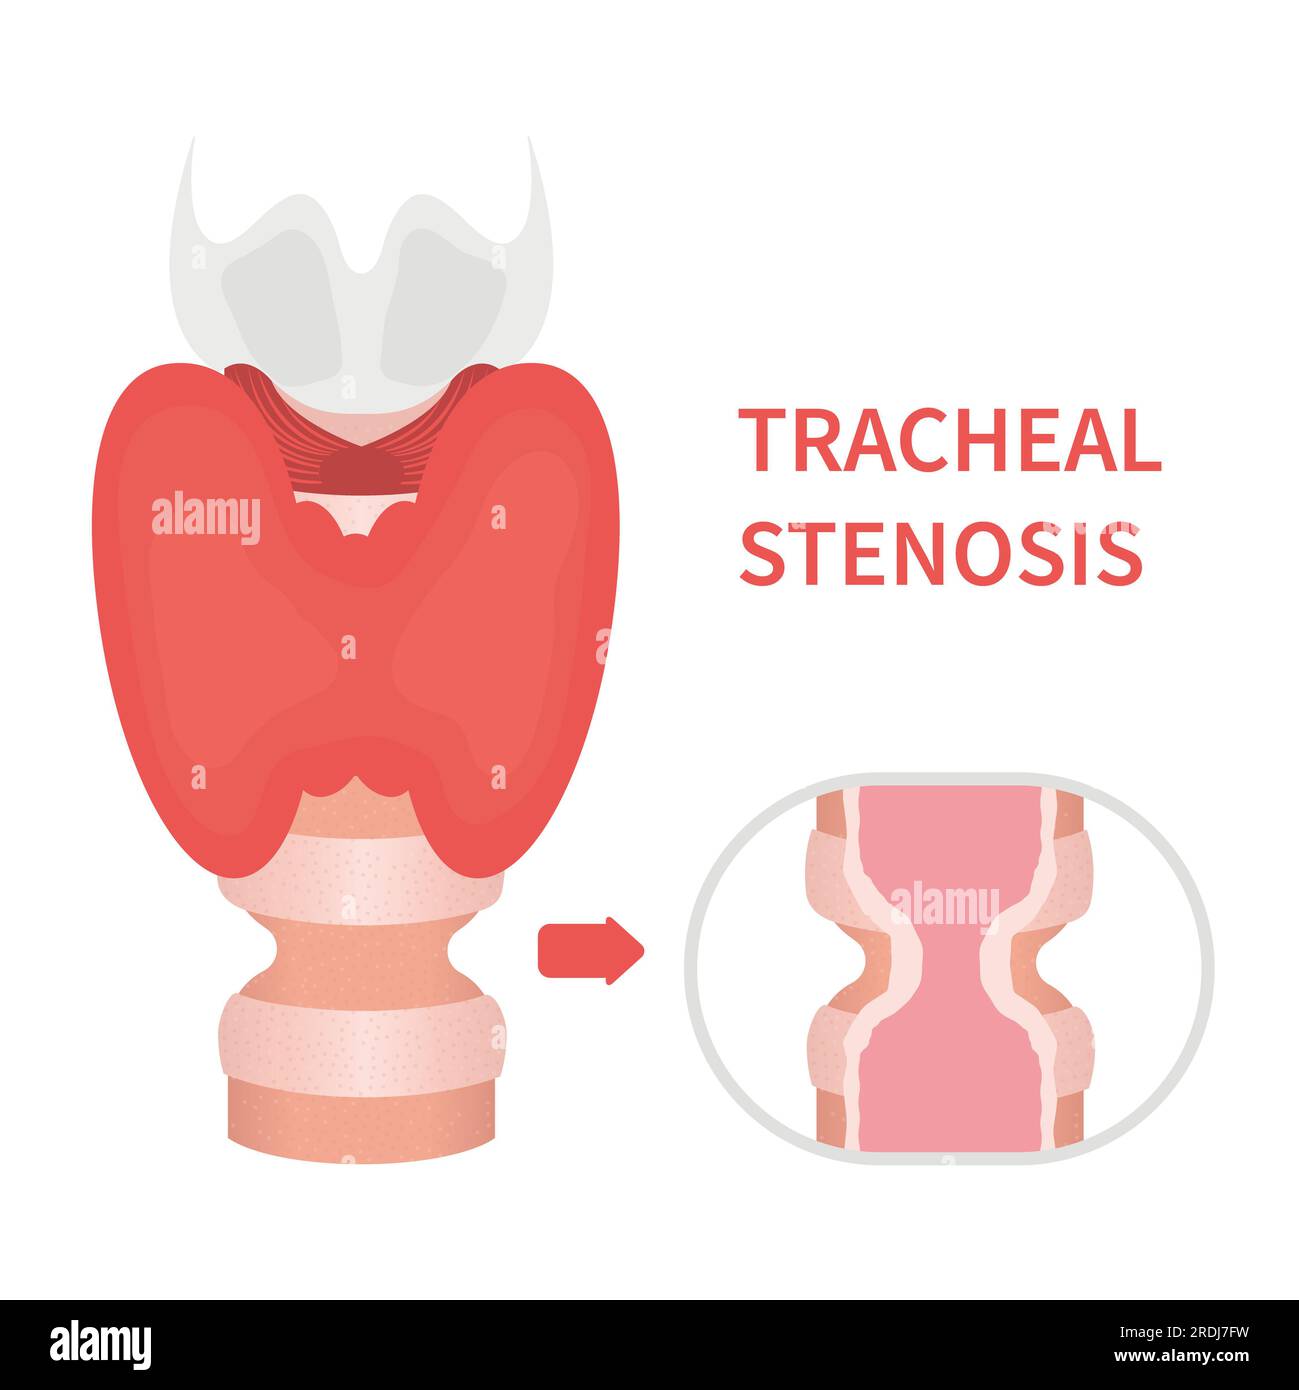

Tracheal stenosis, illustration Stock Photohttps://www.alamy.com/image-license-details/?v=1https://www.alamy.com/tracheal-stenosis-illustration-image559123361.html

Tracheal stenosis, illustration Stock Photohttps://www.alamy.com/image-license-details/?v=1https://www.alamy.com/tracheal-stenosis-illustration-image559123361.htmlRF2RDJ7FD–Tracheal stenosis, illustration

Tracheal stenosis, illustration Stock Photohttps://www.alamy.com/image-license-details/?v=1https://www.alamy.com/tracheal-stenosis-illustration-image559123373.html

Tracheal stenosis, illustration Stock Photohttps://www.alamy.com/image-license-details/?v=1https://www.alamy.com/tracheal-stenosis-illustration-image559123373.htmlRF2RDJ7FW–Tracheal stenosis, illustration

Tracheal stenosis, illustration Stock Photohttps://www.alamy.com/image-license-details/?v=1https://www.alamy.com/tracheal-stenosis-illustration-image559123343.html

Tracheal stenosis, illustration Stock Photohttps://www.alamy.com/image-license-details/?v=1https://www.alamy.com/tracheal-stenosis-illustration-image559123343.htmlRF2RDJ7ER–Tracheal stenosis, illustration

Tracheal stenosis, illustration Stock Photohttps://www.alamy.com/image-license-details/?v=1https://www.alamy.com/tracheal-stenosis-illustration-image559123335.html

Tracheal stenosis, illustration Stock Photohttps://www.alamy.com/image-license-details/?v=1https://www.alamy.com/tracheal-stenosis-illustration-image559123335.htmlRF2RDJ7EF–Tracheal stenosis, illustration

Tracheal stenosis, illustration Stock Photohttps://www.alamy.com/image-license-details/?v=1https://www.alamy.com/tracheal-stenosis-illustration-image559123334.html

Tracheal stenosis, illustration Stock Photohttps://www.alamy.com/image-license-details/?v=1https://www.alamy.com/tracheal-stenosis-illustration-image559123334.htmlRF2RDJ7EE–Tracheal stenosis, illustration